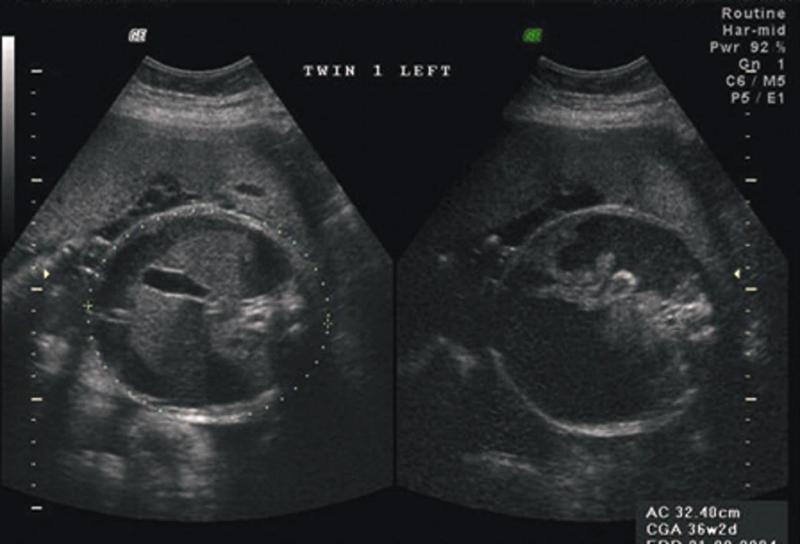

Cross-over fusion kidneys